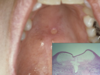

recurrent aphthous stomatitis

34